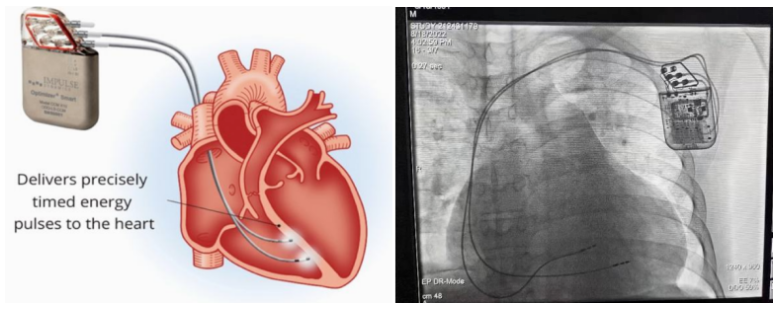

①植入式心臟復(fù)律除顫器

Implantable Cardioverter Defibrillator,ICD

植入式心臟復(fù)律除顫器是一種具有除顫功能的高級(jí)起搏器,是一種體積小、能植入患者胸部皮下組織的醫(yī)療設(shè)備。慢性心衰患者易發(fā)生室性心動(dòng)過速或心室顫動(dòng),導(dǎo)致心源性猝死(SCD)。ICD 則能在幾秒內(nèi)自動(dòng)識(shí)別并治療快速室性心律失常,通過低能量心臟轉(zhuǎn)復(fù)和高能量除顫等功能,顯著降低惡性室性心律失常引起的猝死風(fēng)險(xiǎn)??杉皶r(shí)自動(dòng)為患者轉(zhuǎn)復(fù)心律,通俗地說就是裝在體內(nèi)的自動(dòng)除顫儀。